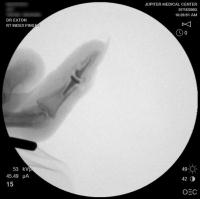

Intraoperative fluoroscopy.

Broach.

Intraoperative fluoroscopy using the same technique as above. The trial spacers: